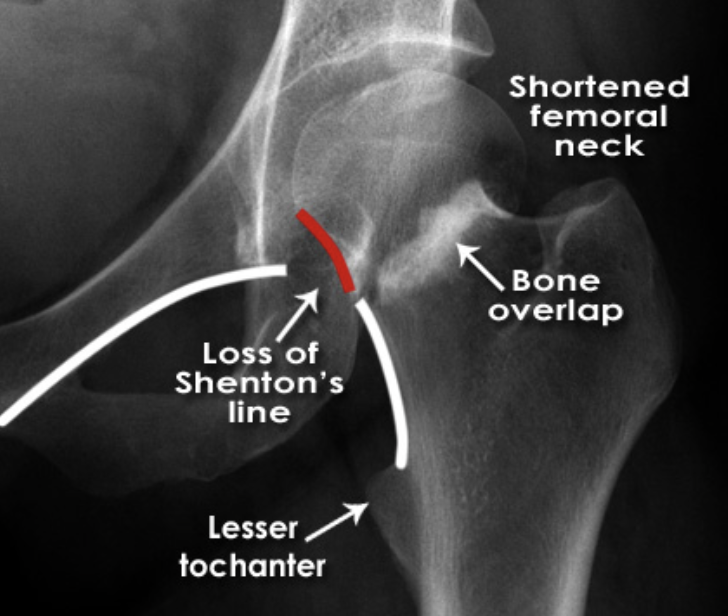

Intracapsular fracture - Subcapital - AP:

1. Shortened femoral neck

2. Increased density of femoral neck (due to impacted bone)

3. Less troch. is more prominent

4. Shenton’s line is disrupted